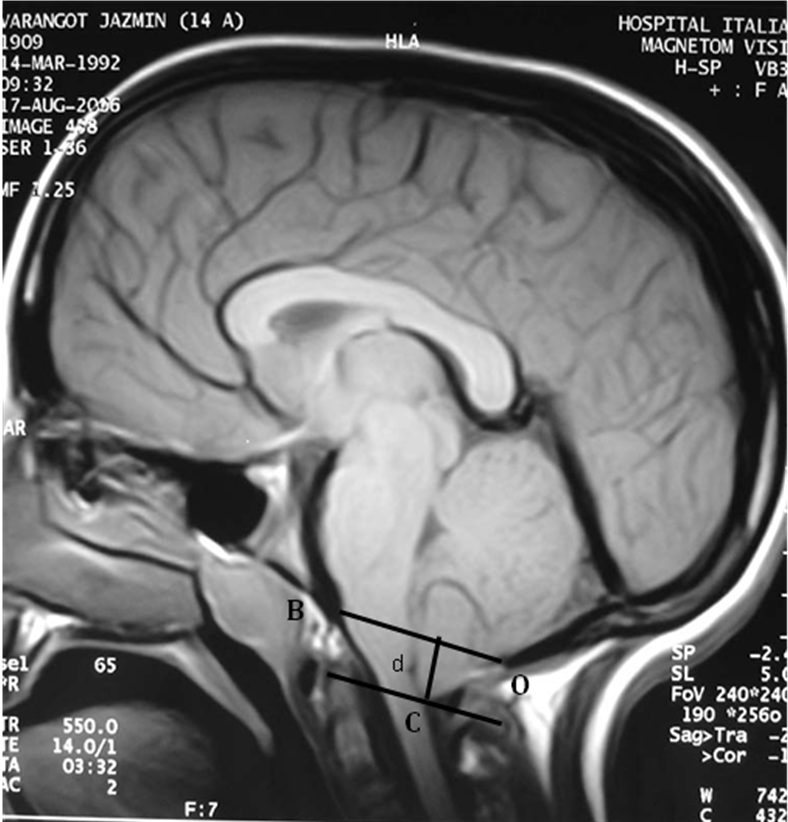

Introducción: El objetivo de este estudio fue analizar las variaciones de posición de la Amígdala Cerebelosa, con resonancia nuclear magnética, antes y después de la corrección de la deformidad espinal mediante una artrodesis vertebral posterior instrumentada (AVP) en pacientes con escoliosis idiopática del adolescente (EIA) que no presentaban sintomatología neurológica.Materiales y métodos: Se evaluaron retrospectivamente 40 pacientes con EIA que no presentaban síntomas neurológicos y a los cuales se les realizó una AVP instrumentada para corregir la deformidad espinal. Se realizó RNM de la fosa cerebral posterior y de la columna cervical en todos los pacientes antes y después de la cirugía espinal. El nivel de la amígdala cerebelosa con respecto al foramen magnum se midió con el método descripto por Aboulezz et al 3.Resultados: La magnitud pre-operatoria promedio de la curva escoliótica fue de 53,15° (DS 10,46°) y de la cifosis torácica fue de 35,42º (DS 12,38°). En el post-operatorio inmediato la magnitud promedio fue de 7,45º (DS 7,33°) y de 27,87º (DS 9,03°), respectivamente. La corrección promedio lograda con la AVP fue de 86% en el plano coronal (p<0.00001). El valor promedio de la longitud de la columna en el plano coronal fue de 44,5 cm (SD 5,25 cm) en el pre-operatorio y de 48,27 cm (DS 4,40 cm) en el post-operatorio (p<0.00001). El valor promedio de la longitud de la columna vertebral en el plano sagital fue de 50,87 cm (DS 4,47 cm) en el pre-operatorio y de 55,13 cm (DS 3,27 cm) en el post-operatorio (p<0.00001). No se observó una diferencia significativa respecto de la posición de la amígdala cerebelosa en las mediciones realizadas antes y después de corregida la deformidad espinal. (p=0,6042). En 10 de los 40 pacientes, se observó un desplazamiento caudal de la amígdala cerebelosa luego de realizada la AVP. En 21 pacientes no se observó ninguna variación en la posición de la amígdala cerebelosa, y en 2 se observó un desplazamiento cefálico de la misma.Conclusión: No observamos una variación significativa de la ubicación de la amígdala cerebelosa respecto del agujero occipital en pacientes con EIA que fueron sometidos una AVP instrumentada para corregir la deformidad espinal. No se encontró correlación entre la magnitud dDescargas

Aboulezz AO, Sartor K, Geyer CA, et al. Position of cerebellar tonsils in normal population and in patients with Chiari malformation: a quantitative approach with MR imaging. J Comput Assist Tomogr 1985;9:1033–6.